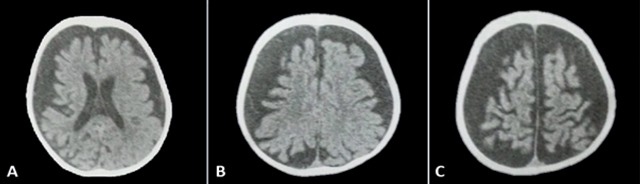

It can be diagnosed by the finding of typical clinical symptoms and by the facial appearance of the port-wine stain 11. ?All patients with facial nevus should undergo radiological evaluation to rule out SWS?, which can be helpful in detecting the classic intracranial calcifications in these patients 1 ( Figure 2).

However, multiple radiological findings have been seen such as atrophy of cerebral lobes, hypertrophy of choroid plexuses, enlargement of deep cerebral veins, venous drainage abnormalities and recently an asymmetric enlargement of the cavernous sinus has been described 4, 24( Figure 3).

Imaging tests, such as doppler ultrasound, computed tomography (CT) or magnetic resonance imaging (MRI), can be useful to determine any possible localised vascular malformations in deep tissues, e.g. cerebral vascular malformations or arteriovenous malformations 4, 11. The neuroimaging technique of choice for the diagnosis of SWS is currently MRI with gadolinium contrast, as it can demonstrate the presence of leptomeningeal angiomatosis and determine the degree of involvement of brain structures 4.